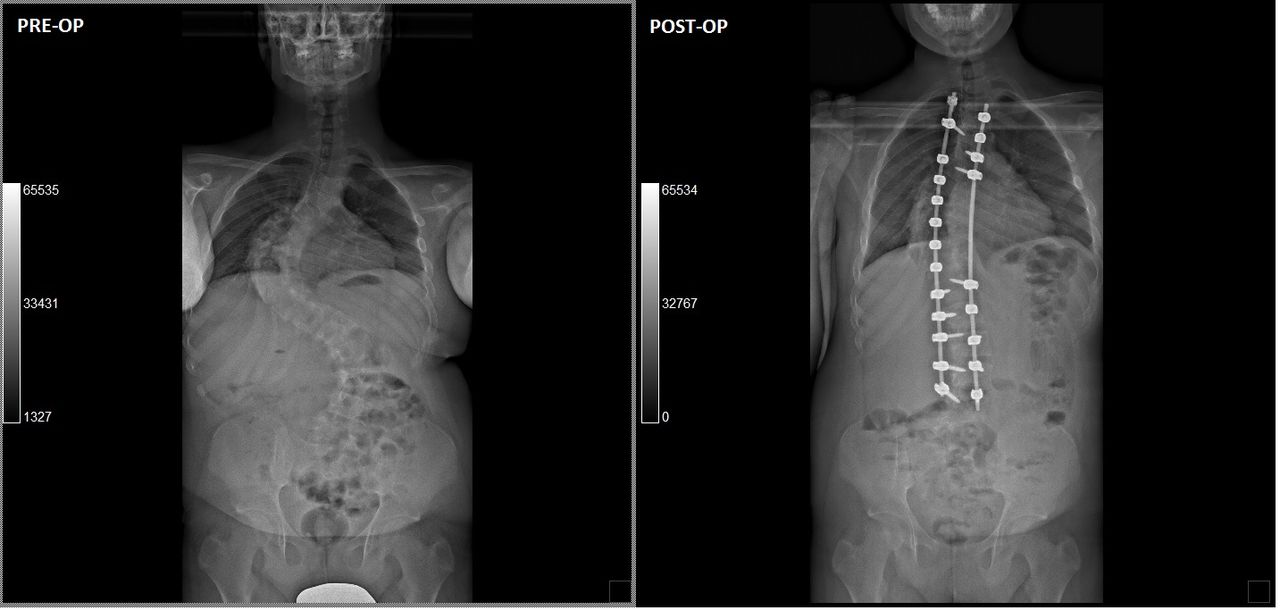

Foto e video